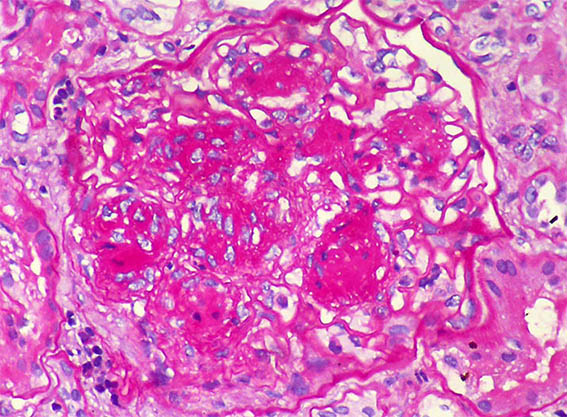

Figure 2. PAS, X400.